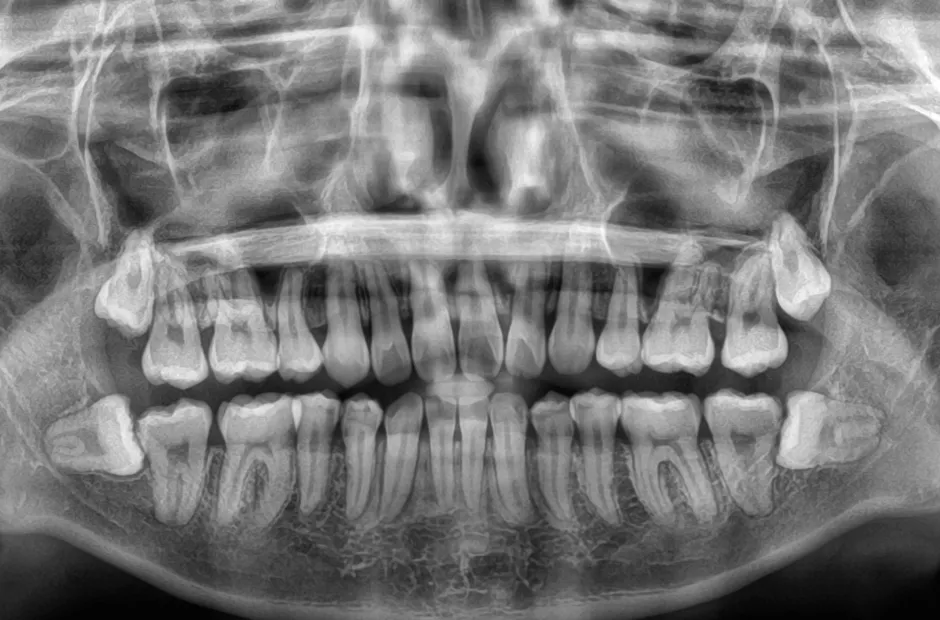

治療前